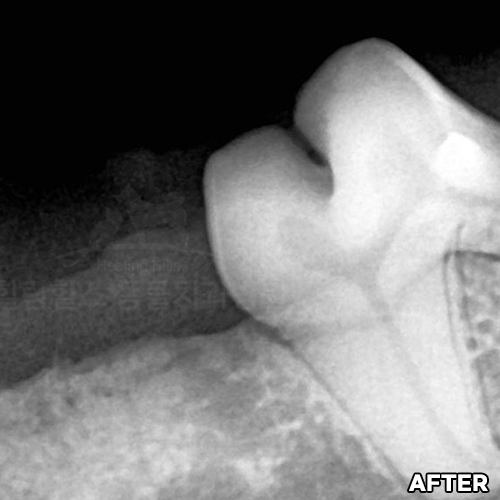

[최소침습적 발치 후 재생된 강아지 잇몸뼈]

샘플